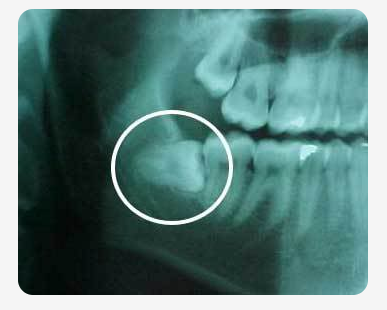

Web Wisdom teeth usually cause pain irritation swelling and infection. Web Position Impacted wisdom teeth may grow sideways or lean against other teeth. Web According to the National Health Service risks associated with local anesthesia may include.